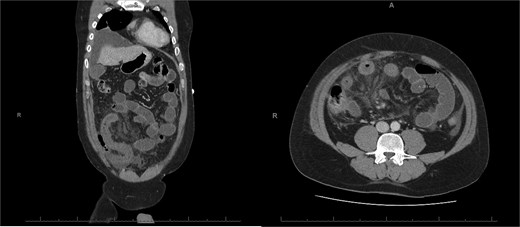

A 76-year-old female with a 3-day history of left upper abdominal pain, vomiting, and haematochezia. Her history included pulmonary embolism, multiple deep vein thromboses, with no ongoing anticoagulation, and an open partial colectomy for complicated diverticulitis a decade earlier. On admission, she was afebrile but tachycardic and showed localized tenderness in the left hypochondrium. Laboratory revealed leucocytosis with a white blood cell count (WBC) of 12 G/L, elevated C-reactive protein (CRP) of 46 mg/L, and hyperlactatemia of 2.6 mmol/l. Enhanced computed tomography (E-CT) revealed jejunal venous ischemia in the left upper quadrant, secondary to extensive porto-mesenteric thrombosis with reduced bowel wall enhancement, distention, and free intraperitoneal fluid (Fig. 1). She was managed conservatively with unfractionated heparin (UFH) with a bolus of 5000 U/l followed by 30 000 U/l/24 h (target INR 0.35–0.7), Piperacillin-Tazobactam, and bowel rest. After 48 h of monitoring in the intensive care unit (ICU), she exhibited marked biological and clinical improvement. E-CT on the third day showed restored bowel wall enhancement and stable porto-mesenteric thrombosis (Fig. 2). She was discharged on therapeutic low molecular weight heparin (LMWH) with enoxaparin sodium 120 mg every 12 h. At the 3-month follow-up, E-CT revealed near-complete thrombus resolution, without intestinal sequelae (Fig. 3).

Abdominal E-CT of the first patient at admission. The white arrows indicate extended porto-mesenteric thrombosis, while the dashed arrows reveal jejunal venous ischemia with a lack of bowel wall enhancement, bowel distension, and free fluid.